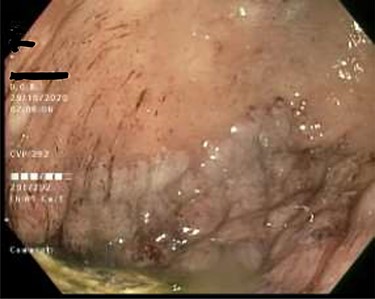

As work up for his abdominal pain and anemia he underwent gastroscopy on 29 October 2020 that revealed congested and nodular gastric mucosa (mass-like) and at lesser extend in the first and second part of duodenum (Figs 1 and 2). Biopsies were taken from the gastric lesion and duodenum. Histopathological findings from gastric mass and duodenum showed marked stromal hyalinosis, which appeared as a cellular pink material on H&E stain (Figs 3 and 5). Congo red stain (amyloid stain) showed apple green birefringence under polarized light on both gastric and duodenal biopsies (Figs 4 and 6).

Gastric mucosa seen by endoscopy as nodular, prominent and congested.